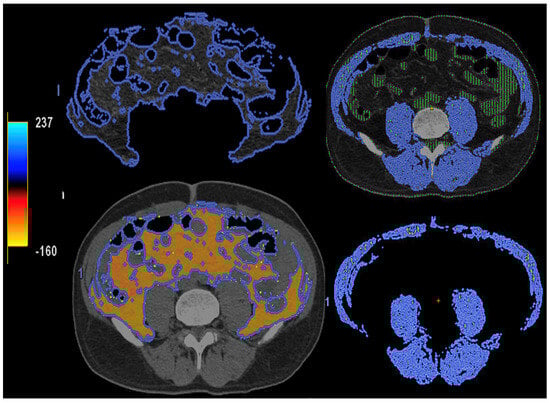

Figure 14. Lymph node (LN) imaging. Color-coded iodine maps of a left (L) axillary malignant LN (yellow arrow and yellow spectral curve, 1), which shows increased iodine uptake compared to a contralateral right (R) benign LN (blue arrow and blue spectral curve, 2). - Imaging of body composition is another growing application of DECT imaging that can be used to improve the evaluation of muscle tissue, visceral adipose tissue (VAT), and subcutaneous adipose tissue (SAT) compartments. SAT and VAT assessment is of special interest in diseases related to metabolic syndrome and critically ill patients [46]. Moreover, sarcopenia is associated with a poorer prognosis in cancer patients [47]. Measuring fat fraction of the skeletal muscle by DECT is a new approach for the determination of muscle quality, an important parameter for the diagnostic confirmation of sarcopenia [48]. In the case of bone mineral density analysis, DECT can provide a more detailed analysis when compared with dual X-ray absorptiometry [49] (Figure 15). Finally, DECT can also be a useful tool for evaluating silicone implants (Figure 16). Silicone contains the heavier element silicon (Z value = 14), whereas soft tissue predominantly comprises lighter elements, depicting the presence of silicone within the soft tissues in cases of silicone gel breast implant rupture and LN silicone spread [50].

Figure 15. DECT-based segmentation of intraabdominal fatty tissue (orange areas) (left column) and segmentation of skeletal muscle volume (right, blue color).